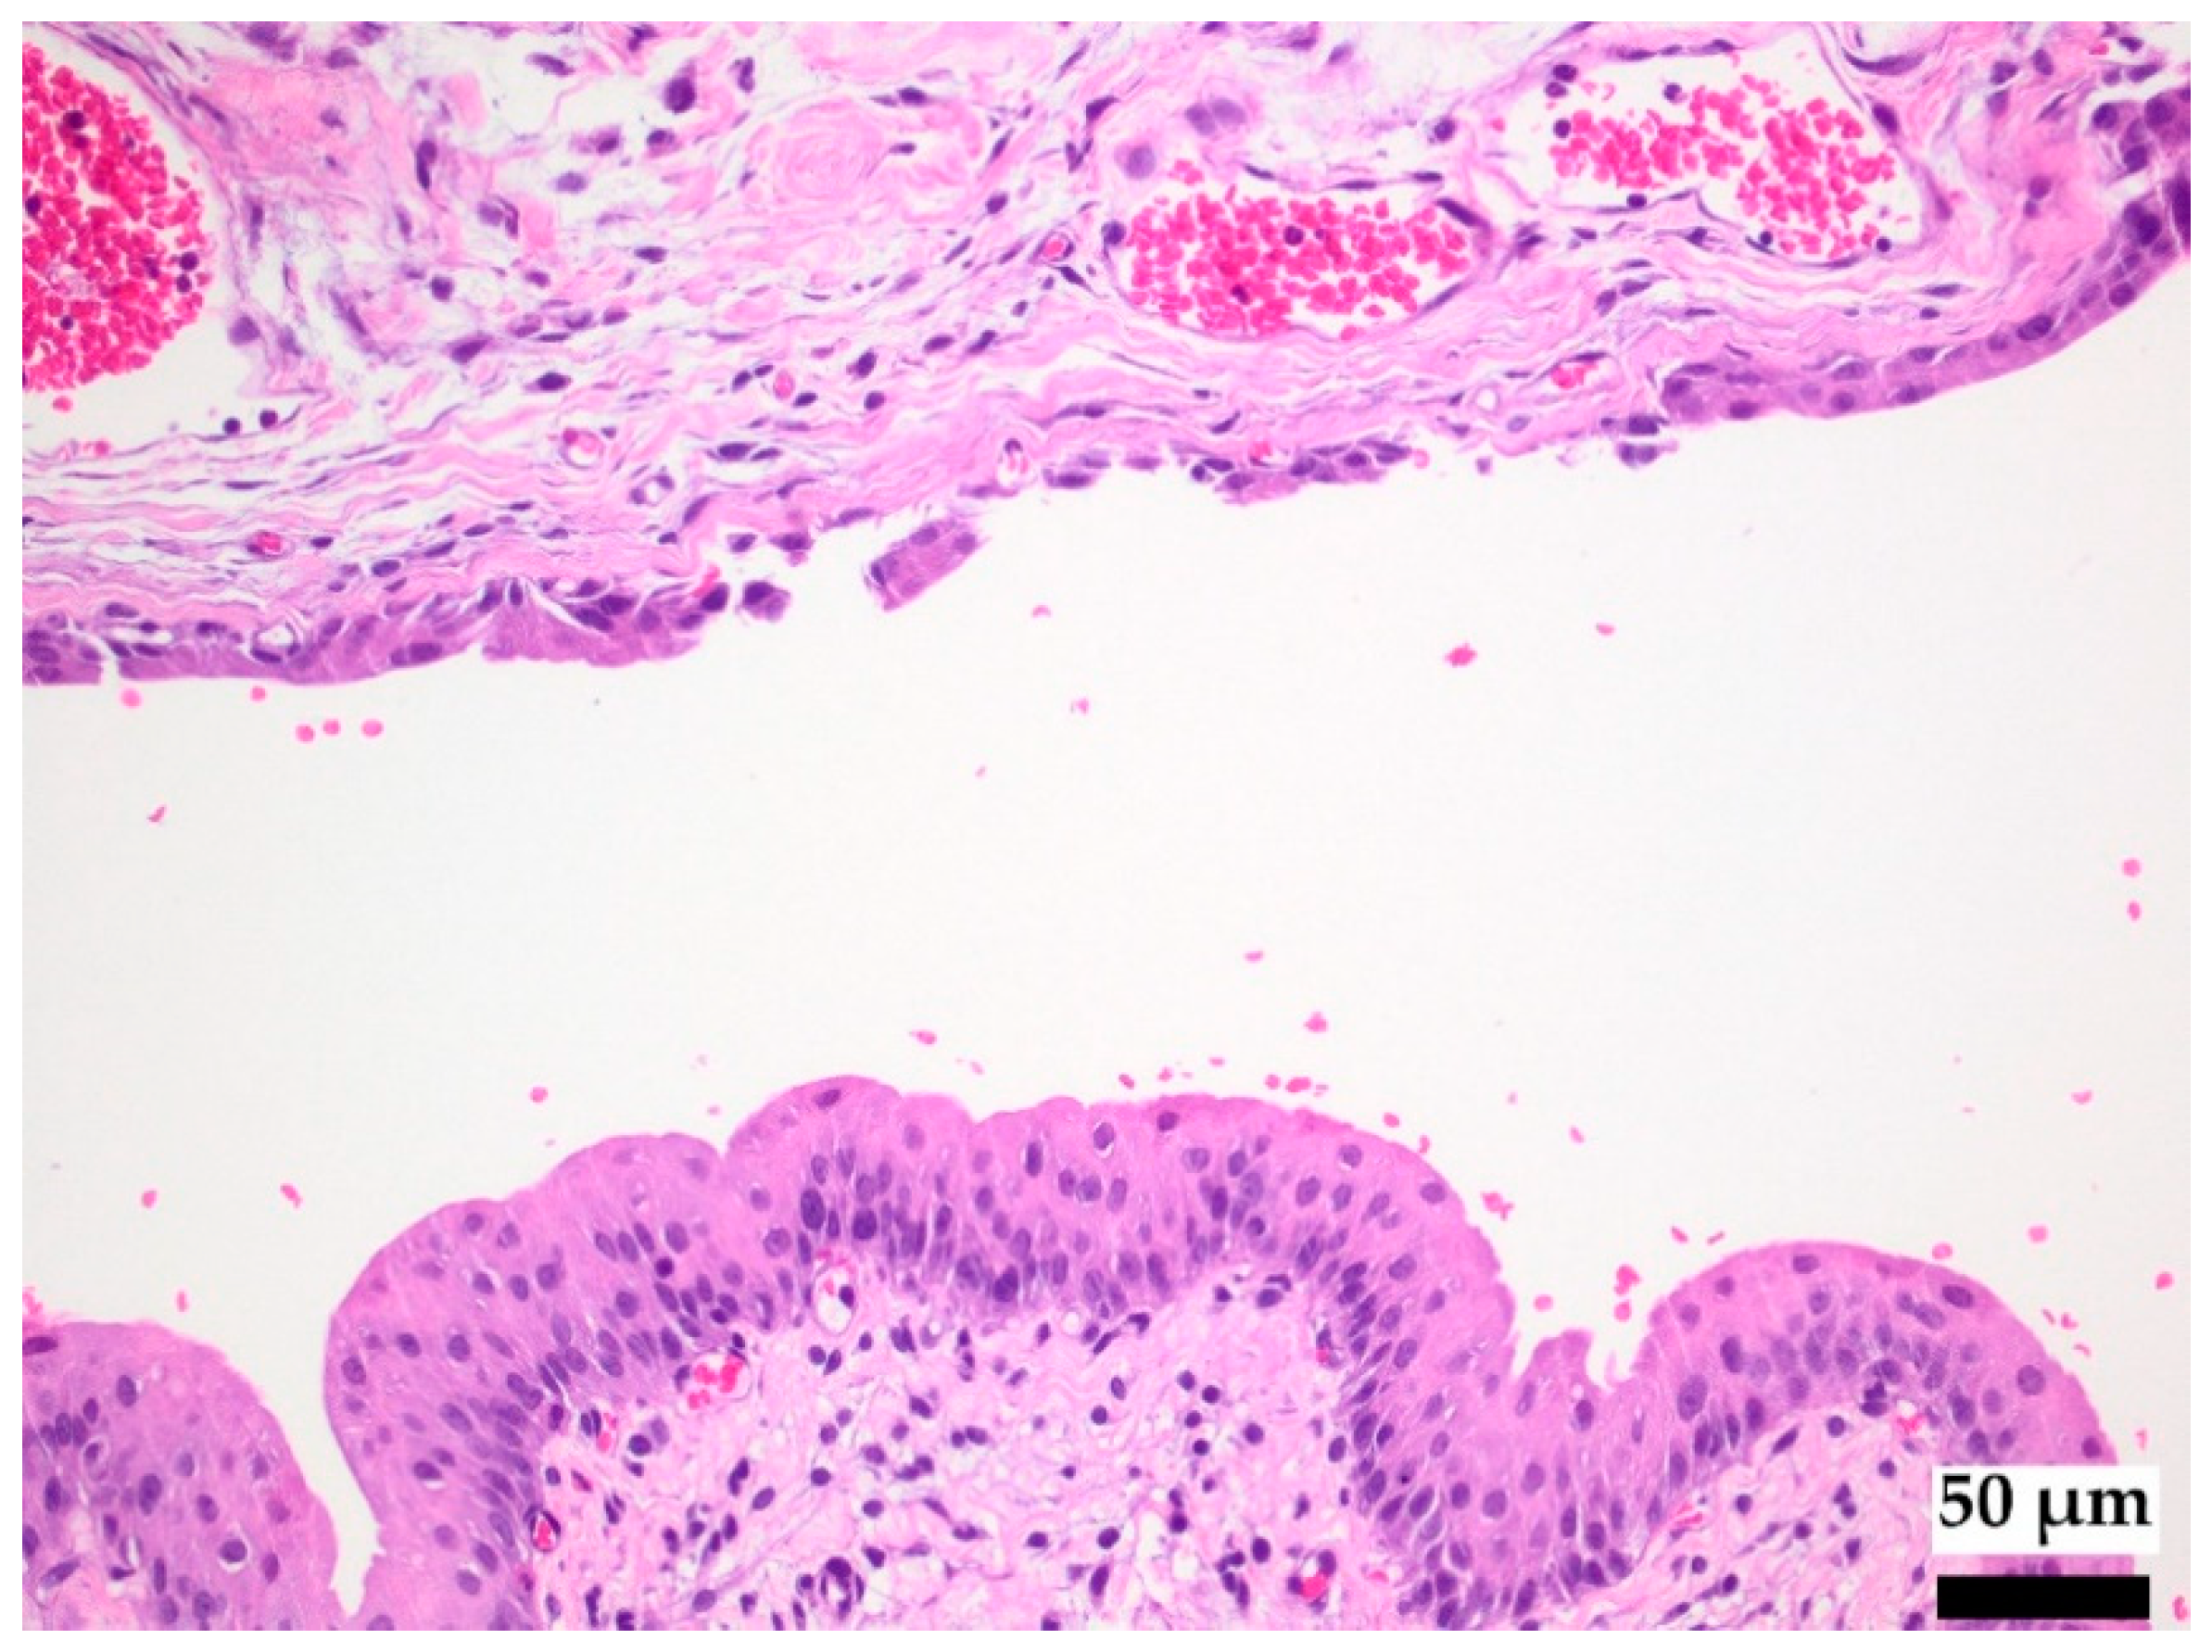

3.2.1. Interaction of Copper-Doped Implants with the Tissue of the Urinary Tract

- Wolf, J.S., Jr.; Humphrey, P.A.; Rayala, H.J.; Gardner, S.M.; Mackey, R.B.; Clayman, R.V. Comparative ureteral microanatomy. J. Endourol. 1996, 10, 527–531. [Google Scholar] [CrossRef]